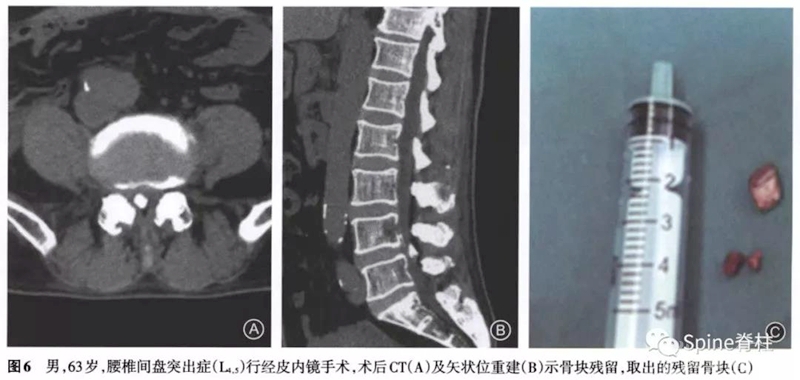

PTED术后常见的并发症,如术中神经根刺激或损伤、术后血肿、术中硬膜囊撕裂、术后椎间盘髓核残留或复发等,大家都比较熟知。然而,一种少见的可能并发症(即症状性关节突关节骨块残留,symptomatic facet of residual bone mass)开始受到关注,有学者认为PTED术中于关节突关节进行椎间孔成形操作属于盲视下操作,即使应用术中X线透视,仍无法精确控制骨块移除的量,因此出现关节突关节骨块残留有一定的可能性。

所有7例患者在经皮内镜手术中均进行了椎间孔成形操作。5例为术后立即出现症状,1例为术后1周出现症状,1例为术后1个月出现症状。经保守治疗后,1例患者症状好转拒绝手术,2例出现对侧的刺激症状,余4例均为原症状加重。其中因残留骨块刺破硬膜囊出现脑脊液漏者2例,残留骨块损伤神经引起下肢肌力下降1例。术后CT提示5例骨块在椎问孔成形同侧,2例在对侧。

术后至翻修时间最短为2d,最长为3个月。翻修术式:2例为椎间盘镜手术,1例为可动式椎间盘镜手术,1例为小切口开窗减压术,1例为经皮内镜手术,1例为微创经椎间孔入路腰椎椎体间融合术。